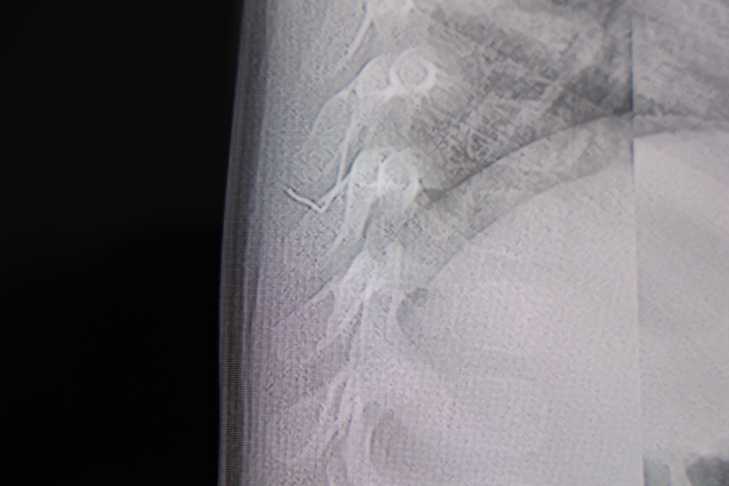

Alınan bilgiye göre, Kahramanmaraş'ta farklı ortopedi, çocuk cerrahisi ve beyin cerrahisi kliniklerine başvurusu yapılan bir yaşındaki bebeğin, sırt bölgesinde yabancı bir cisim olduğu ancak müdahalenin zor olduğu ve 8 yaşına kadar beklenmesi gerektiği bildirildi. Aile, bebekleri için son olarak HG Hospital'e başvurdu. HG Hospital Beyin ve Sinir Cerrahisi Uzmanı Prof. Dr. İdris Altun tarafından yapılan tetkiklerde, yabancı cismin cilt altında, omurilik kanalına yakın bir bölgede olduğu ve akciğer zarına doğru ilerlediği belirlendi. Hasta, genel anesteziye alınmadan, lokal anestezi ve sedasyon eşliğinde ameliyata alındı. Yapılan müdahalede yabancı cisim tamamen çıkarıldı. Çıkarılan cismin, ince zımba teline benzer metal bir tel olduğu ve yaklaşık 2 santimetre uzunluğunda bulunduğu tespit edildi. Hasta, aynı gün taburcu edildi.

Konuya ilişkin açıklama yapan Prof. Dr. İdris Altun, "Sırtında yabancı bir cisim olduğu söylenmiş ancak çıkarılamayacağı ve 8 yaşına kadar beklenmesi gerektiği ifade edilmişti. Bize başvurduğunda yaptığımız tetkiklerde, cilt altında, omurilik kanalına çok yakın ve akciğer zarına doğru ilerleyen bir yabancı cisim tespit ettik. Hastamızı tamamen uyutmadan, lokal anestezi ve sedasyon eşliğinde müdahale ederek lezyonu tamamen çıkardık. Çıkardığımız cismin ince zımba teline benzer, yaklaşık 2 santimetre uzunluğunda metal bir tel olduğunu gördük. Bu yabancı cisim alınmasaydı, bölgede enfeksiyon gelişebilirdi. Enfeksiyon sonucu omurilik kanalında ciddi hasarlar oluşabilir, çocuk büyüdükçe cismin hareket etmesine bağlı olarak omurilikte zedelenmeler meydana gelebilirdi. Ayrıca yana doğru ilerleyerek akciğer zarına ve akciğere batma riski vardı. Bu da enfeksiyona ve ilerleyen süreçte tümörle karışabilecek tablolara neden olabilirdi. Şu an hastamız gayet sağlıklı. Gerekli kontrolleri yaptık ve aynı gün taburcu ettik" dedi.